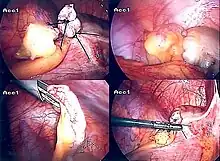

Laparoscopic appendectomy.

Laparoscopic view of a phlegmonous cecal appendix with fibrinous plaques, located in the right iliac fossa.

The surgical procedure for the removal of the appendix is called an appendectomy. Appendectomy can be performed through open or laparoscopic surgery. Laparoscopic appendectomy has several advantages over open appendectomy as an intervention for acute appendicitis.[84]

Laparoscopic appendectomy

Laparoscopic appendectomy was introduced in 1983 and has become an increasingly prevalent intervention for acute appendicitis.[88] This surgical procedure consists of making three to four incisions in the abdomen, each 0.25 to 0.5 inches (6.4 to 12.7 mm) long. This type of appendectomy is made by inserting a special surgical tool called a laparoscope into one of the incisions. The laparoscope is connected to a monitor outside the person's body, and it is designed to help the surgeon to inspect the infected area in the abdomen. The other two incisions are made for the specific removal of the appendix by using surgical instruments. Laparoscopic surgery requires general anesthesia, and it can last up to two hours. Laparoscopic appendectomy has several advantages over open appendectomy, including a shorter post-operative recovery, less post-operative pain, and lower superficial surgical site infection rate. However, the occurrence of an intra-abdominal abscess is almost three times more prevalent in laparoscopic appendectomy than open appendectomy.[89]